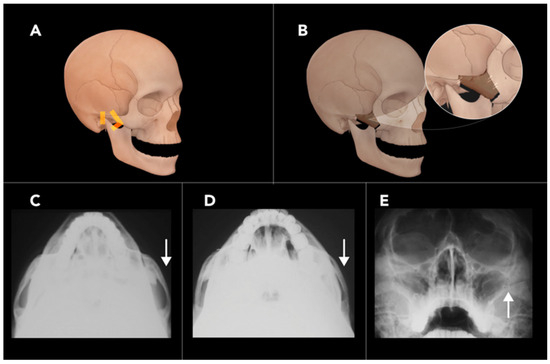

2.1.4. Bilateral Sagittal Split Osteotomy

- Monson, L.A. Bilateral sagittal split osteotomy. In Seminars in Plastic Surgery; Thieme Medical Publishers: Stuttgart, Germany, 2013; pp. 145–148. [Google Scholar]

- Böckmann, R.; Meyns, J.; Dik, E.; Kessler, P. The modifications of the sagittal ramus split osteotomy: A literature review. Plast. Reconstr. Surg. Glob. Open 2014, 2, e271. [Google Scholar] [CrossRef]

- Ylikontiola, L.; Moberg, K.; Huumonen, S.; Soikkonen, K.; Oikarinen, K. Comparison of three radiographic methods used to locate the mandibular canal in the buccolingual direction before bilateral sagittal split osteotomy. Oral Surg. Oral Med. Oral Pathol. Oral Radiol. Endodontol. 2002, 93, 736–742. [Google Scholar] [CrossRef] [PubMed]